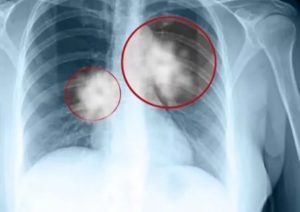

Для ранней диагностики важны результаты флюорографических обследований. В бессимптомном периоде болезнь можно выявить только при помощи лучевой диагностики.

При этом имеют место следующие изменения: шаровидные новообразования, корень легкого и средостение расширены. При пораженном бронхе появляются признаки гиповентиляции участка.

Перибронхиальная форма болезни характеризуется наличием узла в корневом отделе. При периферической форме рака выявляется фокус в пораженном отделе, может быть ярко выделена дорожка от опухоли к корню, иногда отчетливо выделено место вхождения бронха.